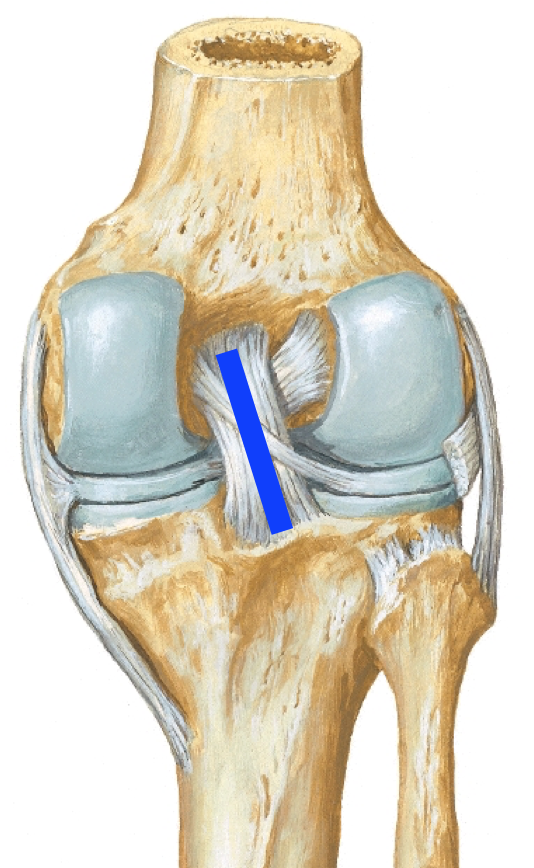

Intraarticular ligaments of knee joint:

IN-PALM

Label:

Anterior cruciate ligament origin and insertion:

APEX

Posterior cruciate ligament origin and insertion:

PAIN